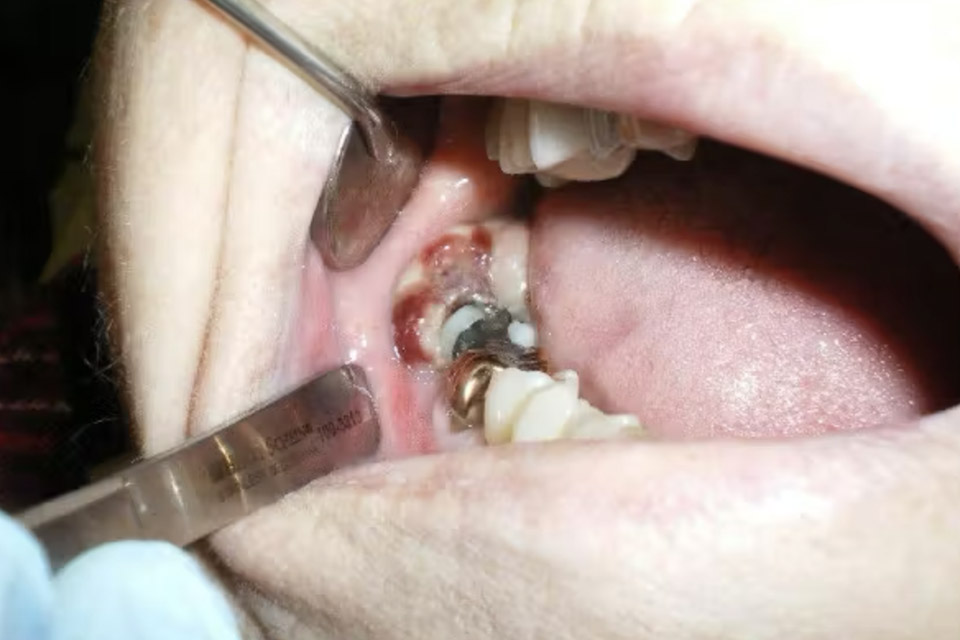

Dù phần lớn các ổ chân răng sót lại không gây vấn đề, vẫn có những bệnh nhân xuất hiện đau nhiều năm sau khi đã nhổ răng. Bouquot và cộng sự (2012) khuyến nghị rằng “khi bệnh nhân có đau, cần thực hiện thêm các xét nghiệm như xạ hình xương, siêu âm định lượng, gây tê chẩn đoán và thăm dò phẫu thuật.” Các tác giả viết: “Điều này rất quan trọng vì các nghiên cứu theo dõi cho thấy nạo bỏ vùng xương thiếu máu hoặc viêm có thể loại bỏ hoàn toàn cơn đau ở 72%–86% bệnh nhân được điều trị.”

Phần lớn các ổ chân răng sót lại không cần can thiệp nếu bệnh nhân không có triệu chứng. Tuy nhiên, nếu có đau kéo dài, nhức sâu hoặc cảm giác khó chịu mạn tính, cần:

- Cân nhắc chuyển bệnh nhân đi phẫu thuật nạo ổ xương thiếu máu hoặc viêm mạn tính.